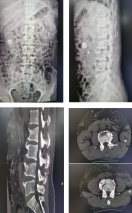

脊柱科

• 颈椎病

• 腰椎间盘突出

• 脊柱侧弯

• 腰肌劳损

• 椎管狭窄

• 椎体滑脱

• 坐骨神经痛

• 腰腿疼痛

• 更多